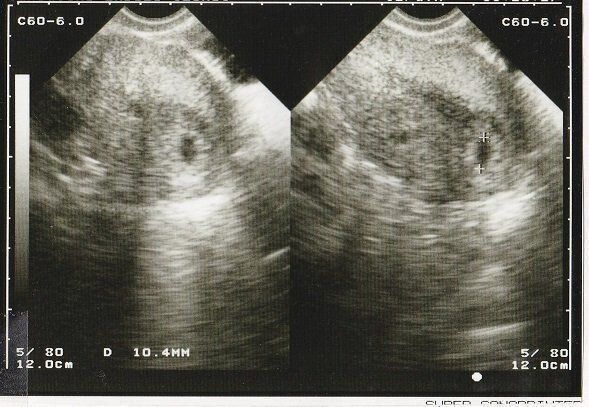

たかこさんの妊娠5週のエコー写真 胎嚢を確認後、不正出血で絶対安静に

めまいを覚えたことから妊娠を疑い、その頃は計算上で妊娠3週目程度だったため、そこから2週間待って病院へ。エコー写真ではまだ胎嚢(中央の小さな縦長の黒い部分)しか確認できません。2度の流産経験から胎嚢を見るのは3回目で、「ぬか喜びをしてはいけない」と自分に言い聞かせていました。この翌日の夜、不正出血があり、自宅で絶対安静と言われました。「気休めだけど」と言われた薬を飲んで、トイレと食事以外は起きない生活が2週間続きました。